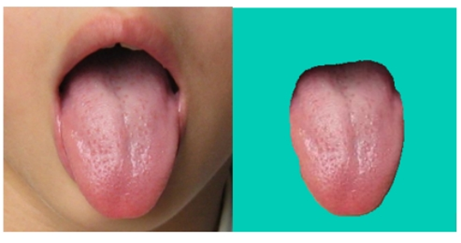

假设我们现在通过上述文章获得了舌体分割好的图片如下图所示:

现在我们就来讨论这个舌体是否倾斜!